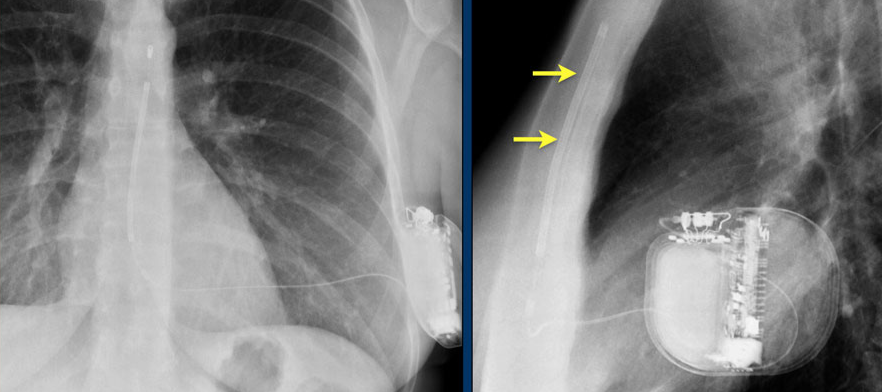

Defibrillateur sous-cutané

- Sonde de défibrillateur pré-sternale

- Ne peut pas faire de fonction de pace